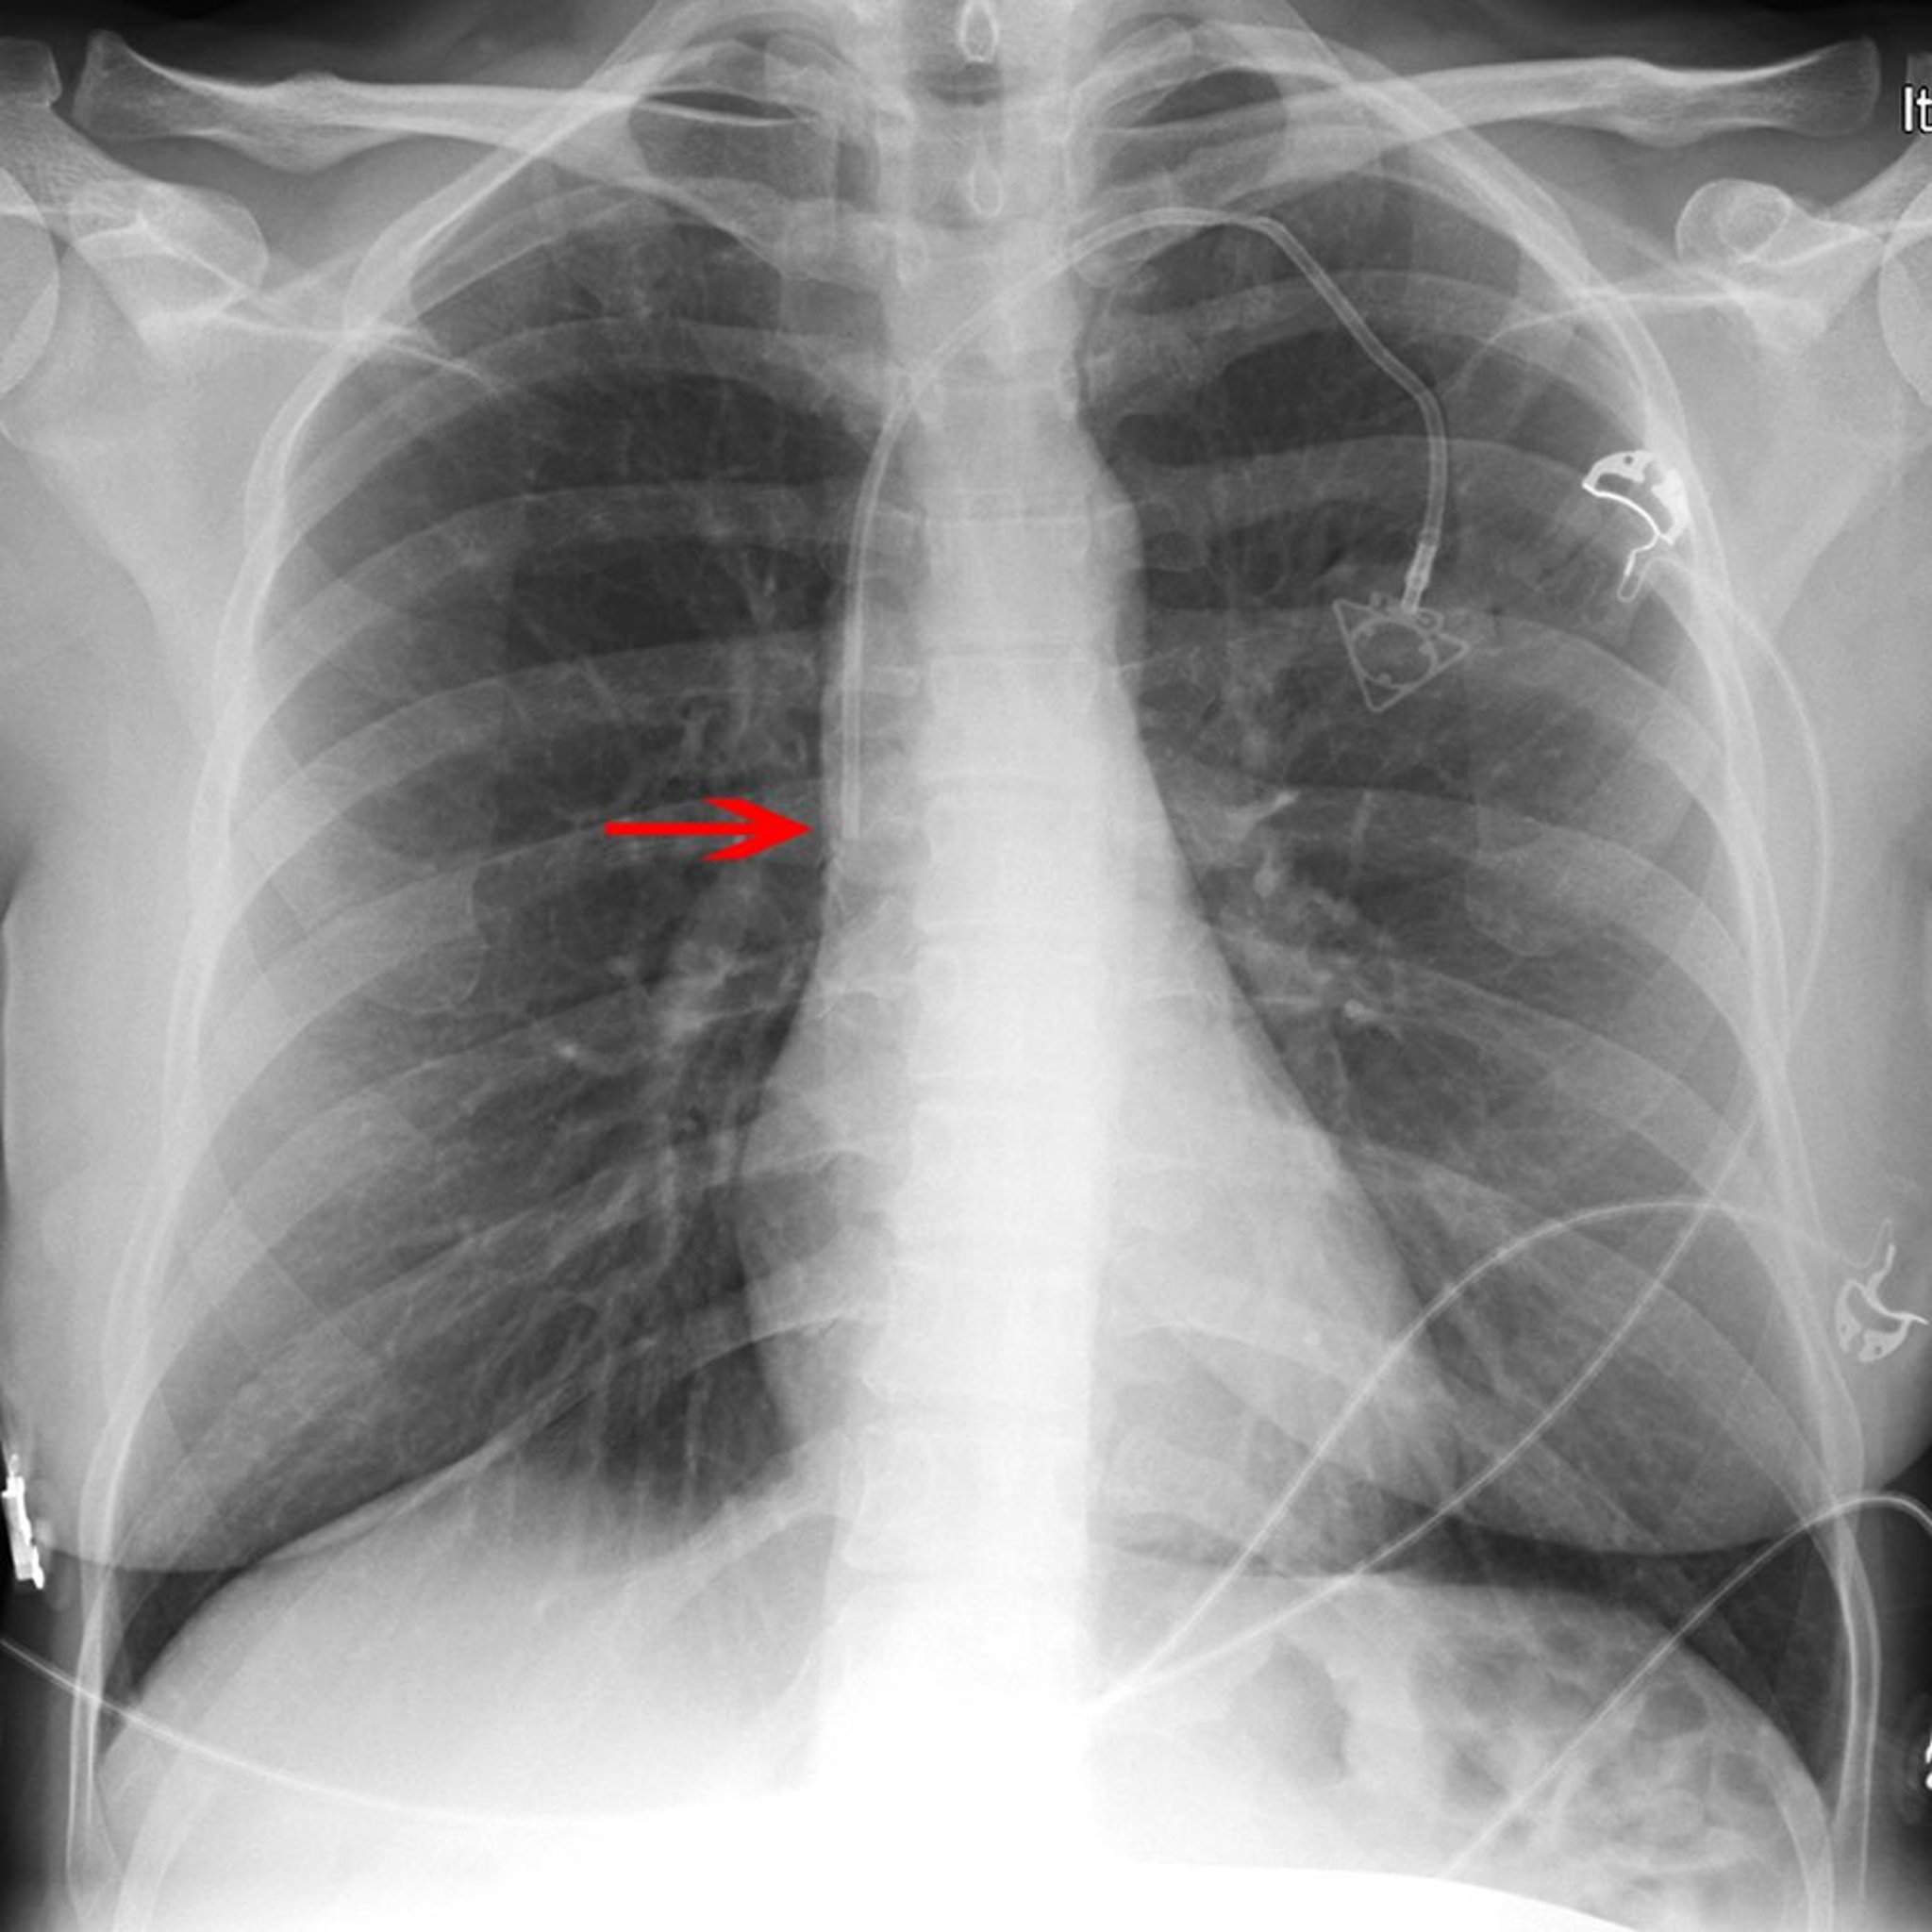

Radiographie d'un cathéter veineux central

La flèche rouge pointe vers l'extrémité d'un cathéter veineux de sous-clavière gauche (placé de manière appropriée en bas de la veine cave supérieure).